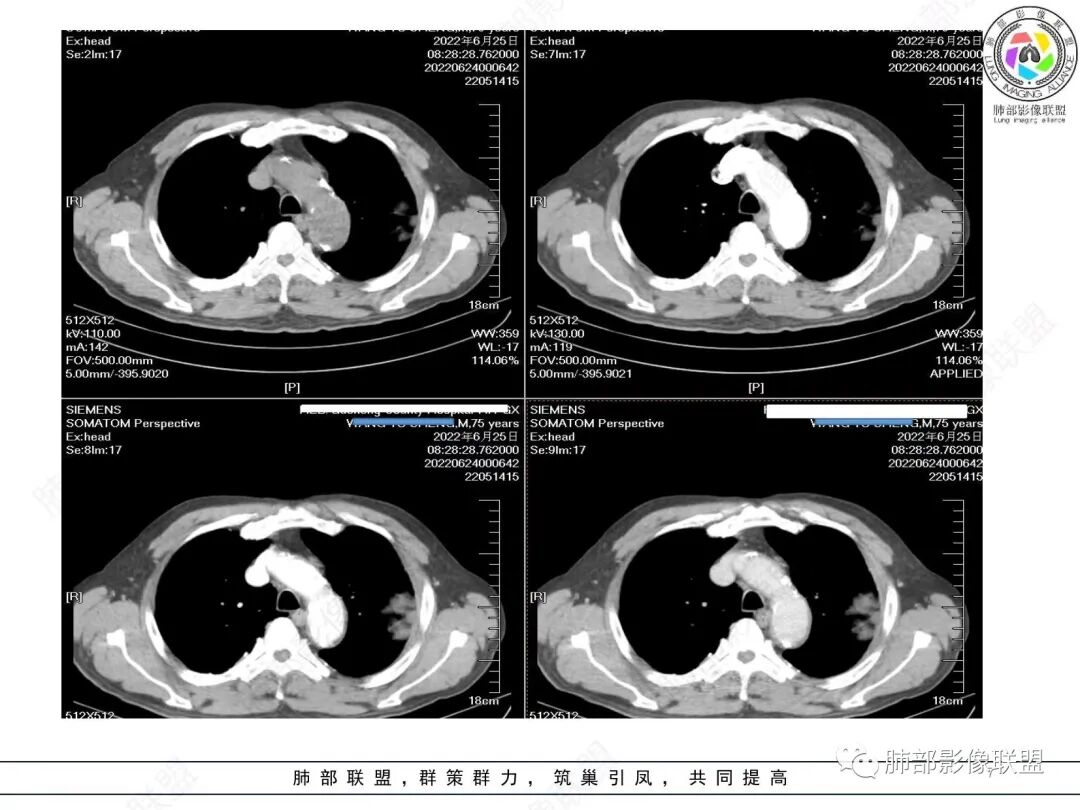

左肺上叶大肿块,膨胀性生长,边界清,密度较低,见部分坏死区,强化弱,肿块见支气管充气V扩张征,分布僵直,枯树枝特点,另一个重要特点血管造影征,淋巴瘤,肿块长轴与胸膜平行,与隐球菌鉴别,隐球荚膜抗原检查,明确诊断经皮肺穿刺。另胸膜钙化(问诊既往有无患胸膜炎病史)。

老年男性,糖尿病病史,消瘦、乏力三个月,影像表现左肺上叶胸膜下团块,有一定张力,内部疏松,可见支气管影及坏死区,增强病灶边缘环形强化,内部未见强化,考虑炎性肉芽肿病变,隐球?奴卡?放线菌?鉴别淋巴瘤。

左肺上叶胸膜下肿块,宽基底与胸膜相连,跨叶裂,边缘清晰膨隆,其内支气管充气,部分扩张、僵直,无明显强化,血管造影征,考虑淋巴瘤,鉴别腺癌

左肺胸膜下巨大占位,跨叶裂,宽基底与胸膜相连,胸膜钙化,平扫密度较低,强化不明显,可见内部血管显影,支气管充气征和扩张,考虑为恶性,倾向于淋巴瘤

我要修正一下观点了:仔细看了视频,肿块占位效应明显,对周围血管,支气管有推挤,增强后强化不明显,NSE增高,半年体重下降25公斤,虽然有内部支气管扩张,血管漂浮,边界清楚支持淋巴瘤,但强化太低,膨隆,占位推挤太明显(淋巴瘤一般没有这么明显的占位效应),胸膜关系有载桩,恶病质明显(乏力,半年体重下降了25公斤),NSE也明显增高,就不支持淋巴瘤了。还是考虑外朝内的恶性肿瘤,间质来源的肉瘤伴有神经内分泌分化或者大神泌。

不支持淋巴瘤的有四点:1、对周围血管支气管推挤明显。2、胸膜有栽桩,3、强化太弱(淋巴瘤一般还是中度以上甚至高度强化多见),4、NSE升高明显,体重下降太明显。

老年男性,糖尿病病史,消瘦、乏力三个月,肿瘤标志物高。左肺上叶胸膜下肿块,边界清晰,可见支气管影及坏死区,增强病灶边缘强化,内部未见明显强化,邻近胸膜有累及,考虑恶性,建议穿刺活检。

1)部位:周围型或中央型软组织肿块,以周围型为多见,且肿瘤多位于肺上叶。如本例:该肿瘤位于左肺上叶。

2)大小及形态:由于本病恶性程度高,早期症状不明显,发现时肿块均较大。如本例病变巨大。

3)肿块边界和边缘:多较清楚,呈圆形、类圆形,且由于肿块生长速度不均匀,可见分叶,毛刺少见。有报道肿块周围毛玻璃影是多形性癌特征表现。

4)密度:肿块平扫为软组织密度,由于体积较大,内部常见大片状坏死,可出现不规则厚壁空洞或坏死内多发无壁小空洞,坏死多不均匀:坏死灶内可见如柳絮样的斑片样强化灶,坏死边缘与非坏死区分界不清本例坏死较明显,密度不均匀。

5)肿瘤强化方式:肺部恶性肿瘤强化程度与其血供丰富程度相关,血供丰富多强化明显,反之则较差。由于PSC 周边实性部分富血供及内部黏液变性、坏死,增强后肿块多数呈轻-中度边缘环形强化或不均匀小斑片状强化。国外学者对照病理发现肿瘤细胞或胶原组织增强扫描时强化,无强化的低密度区代表了黏液样变性区和出血坏死区。